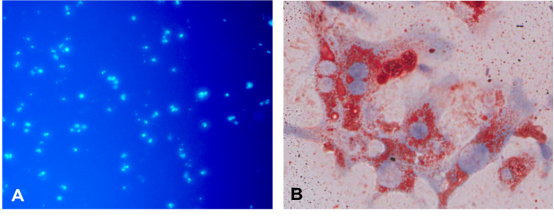

邓志华课题组查阅大量文献资料����,发现肝星状细胞(HSC)在肝纤维化中发挥关键作用�����,此外近年研究还发现HSC具有免疫细胞特征���,直接参与肝脏的免疫调控����,但由于HSC是肝脏的非实质细胞���,数量极少���,分离小鼠原代HSC非常困难���,限制了其研究进展���。课题组经过不断摸索研究����,运用OptiPrep分离液结合原位手工灌注法分离到BALB/c小鼠高纯度高得率的原代HSC��,倒置荧光显微镜下观察���:新分离的HSC呈圆形���,具有丰富的脂滴����,在328nm波长的紫外光激发下自发蓝绿色荧光��,逐渐从圆形变为梭形或星形����,培养7d后����,伸出细长的伪足���。原代HSC油红O染色阳性���,胞浆中的脂滴呈红色��,细胞核呈蓝色���,传2代后免疫细胞化学染色HSC完全表达α-SMA和Desmin����,自发活化����。课题组进一步将BALB/c来源的HSC与C57BL/6小鼠脾脏来源的Treg细胞共培养��,观察HSC对Treg的诱导作用���,异体活化的HSC可在体外呈剂量依赖性����、通过细胞-细胞直接接触方式诱导Treg增殖��,扩增的Treg可有效表达FoxP3��,在体外可有效抑制Teff细胞增殖���。为进一步证实扩增的Treg的免疫调节活性���,将扩增的Treg通过尾静脉注射到ConA诱导的AIH小鼠体内��,观察其对AIH小鼠受损肝脏的影响���,发现扩增的Treg可调节AIH小鼠脾脏Treg/Th17比例失衡��,肝脏炎症和肝细胞坏死明显减轻[图2]���,血清ALT����、AST水平IL-6��、TNFα����、IFN-γ水平降低���,发挥了良好的治疗作用��。该课题为寻找替代糖皮质激素/硫唑嘌呤治疗AIH的免疫细胞疗法提供了可靠的实验研究结果�����。

图1分离的原代肝星状细胞倒置荧光显微镜下自发蓝绿色荧光(A)和油红染色(B)图片